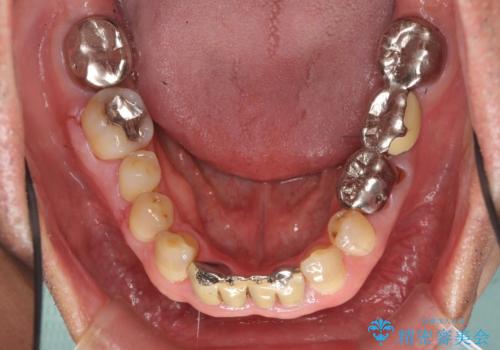

- 105.6万円(インプラント 20万円x2、カスタムアバットメント10万円x2、ジルコニアクラウン10万円x3、仮歯2万円x3)費用は治療当時の料金となります

⑦最終的なセラミッククラウンの装着

となります。